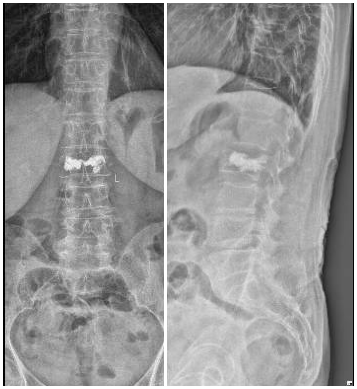

明確診斷后,太原市中心醫院骨科汾東一病區脊柱微創組團隊為患者實施了椎體成形術。術后,患者疼痛明顯減輕,并可下地行走。

骨折壓縮明顯,疼痛癥狀嚴重,可以采用手術治療。目前,椎體成形術已被廣泛用于臨床并取得很好的效果。椎體成形術是在影像指導下,將穿刺針經皮穿刺到病變椎體后,向椎體內注入骨水泥,既可以消除或緩解疼痛癥狀,又能加固和強化椎體從而防止進一步塌陷。